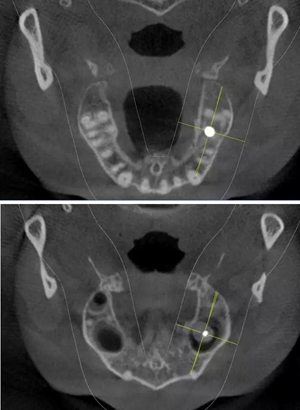

術(shù)前CBCT檢查

骨高度不足,內(nèi)提升的適應(yīng)癥??梢?jiàn)竇膜致密,厚度均勻。骨高度不足,骨寬度尚可。

術(shù)后CBCT